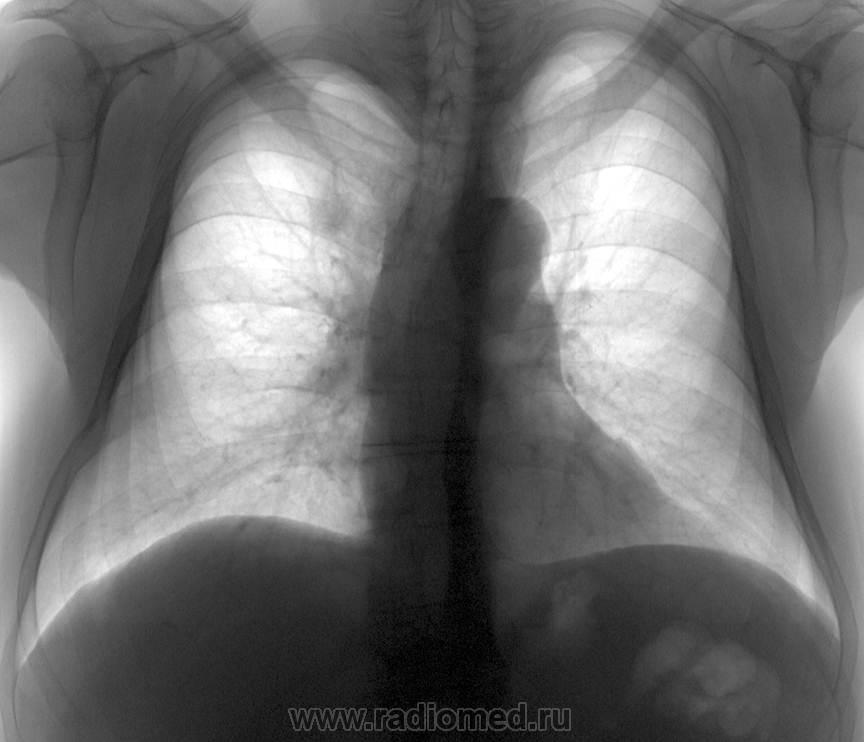

Попробую дополнить. Женщина. Узловой зоб.

Очень показательное дополнение. Спасибо.